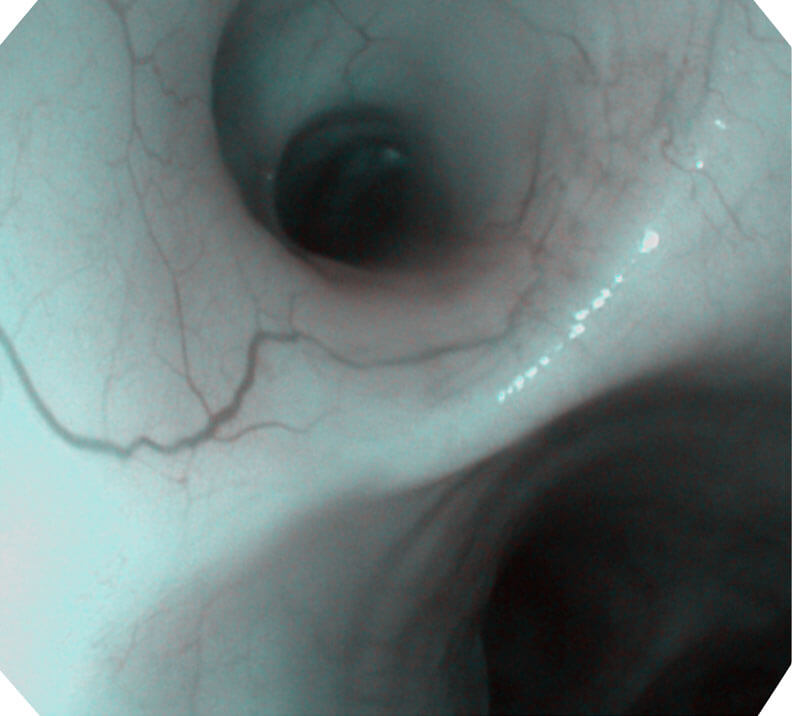

120°视场角,满足更大视野范围的观察。配合 VIST 染色,助力呼吸系统疾病的诊断。

(Versatile Intelligent Staining Technology, VIST)

光电复合染色成像技术(VIST)是一种光学滤波和数字滤波相结合的染色成像技术,摒弃了滤光转轮而直接采用光谱组合的方案,加入了血红蛋白吸收高峰与次高峰的蓝紫光和绿光光谱,更有利于黏膜血管吸收,突显浅表层血管和中层血管的对比度,因而具备更高的图像对比度,有助于观察微细结构变化及病灶边界的观察。